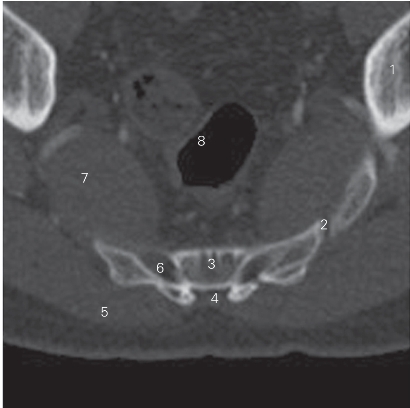

图3-4 经第4骶椎的横断层CT图像(骨窗)

1 髂骨 ilium 2 骶髂关节 sacroiliac joint

3 第4骶椎 4th sacral vertebrae 4 骶管 sacral canal

5 臀大肌 gluteus maximus 6 骶孔 sacral foramen

7 梨状肌 piriformis 8 直肠 rectum